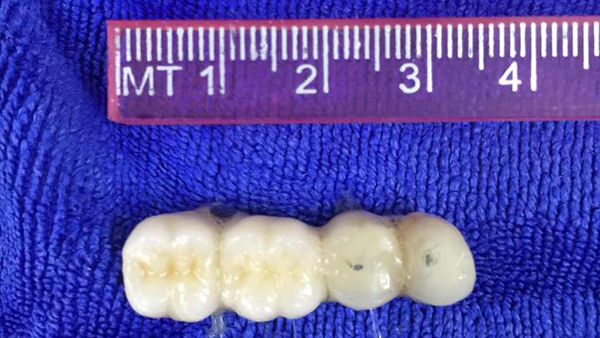

Sau cơn ho, người đàn ông rơi răng giả vào khí quản

Chiếc răng giả bị kẹt trong khí quản người đàn ông sau khi bị ho sặc lúc trên đường đi xe máy. Rất may, bác sĩ đã kịp thời gắp dị vật ra ngoài kịp thời.